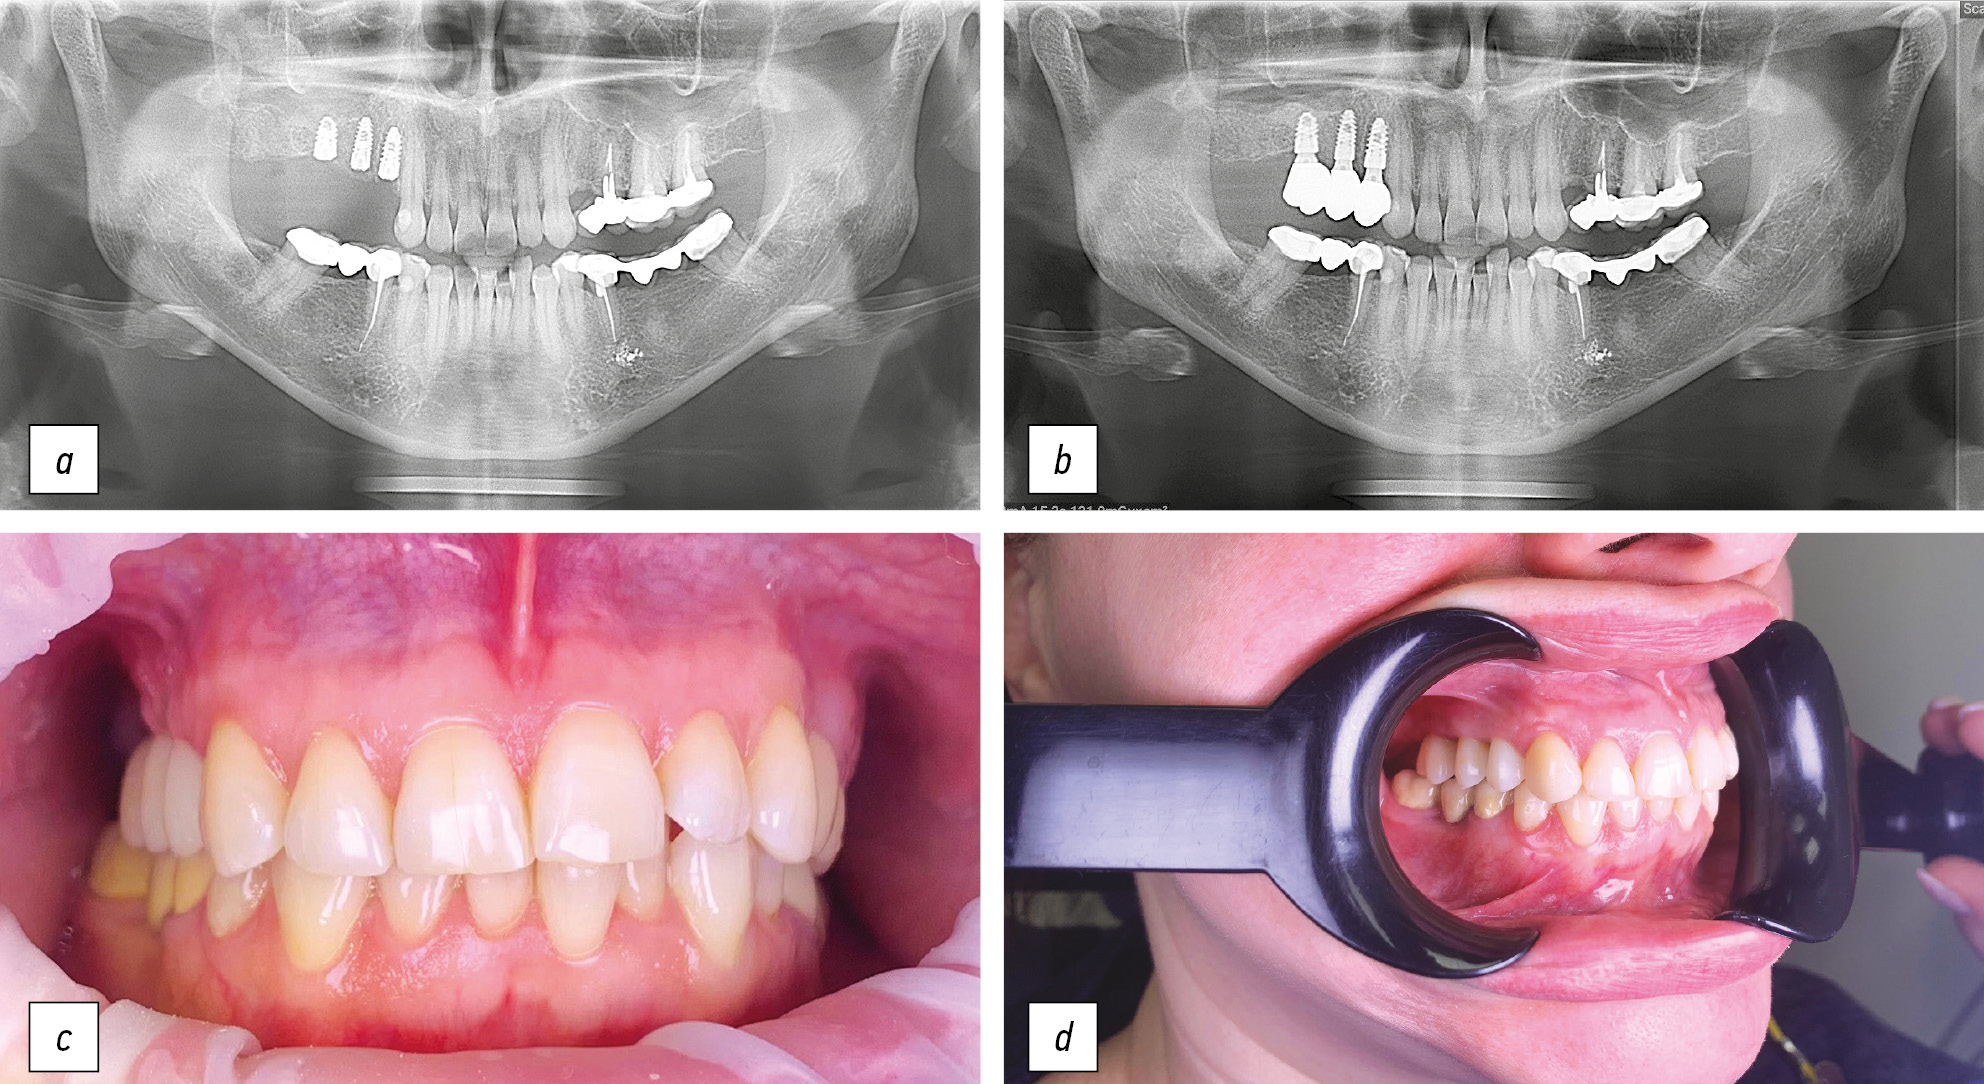

Рис. 2. Этапы стоматологической реабилитации пациентки Л., 37 лет: а — фрагмент ортопантомограммы перед установкой формирователей десневой манжеты; b — фрагмент ортопантомограммы через год после установки постоянной ортопедической конструкции; c — вид полости рта после фиксации окончательной ортопедической конструкции; d — контрольный осмотр пациента через 1,5 года после завершения стоматологической реабилитации.

Fig. 2. Stages of dental rehabilitation of patient L., 37-years-old: a — fragment of an orthopantomogram before the installation of the gingival cuff shapers; b — fragment of an orthopantomogram a year after the installation of a permanent orthopedic structure; c — view of the oral cavity after fixing the final orthopedic structure; d — control examination of the patient 1.5 years after the completion of dental rehabilitation.

После стабилизации мягких тканей периимплантной зоны реализован протокол ортопедического этапа стоматологического лечения и установлены коронки на винтовой фиксации из диоксида циркония. Контрольная ортопантомограмма выполнена через год, контрольный осмотр через 1,5 года после завершения стоматологической реабилитации: наблюдается стабильный профиль костных и мягких тканей, способствующий длительному функционированию ортопедической конструкции.